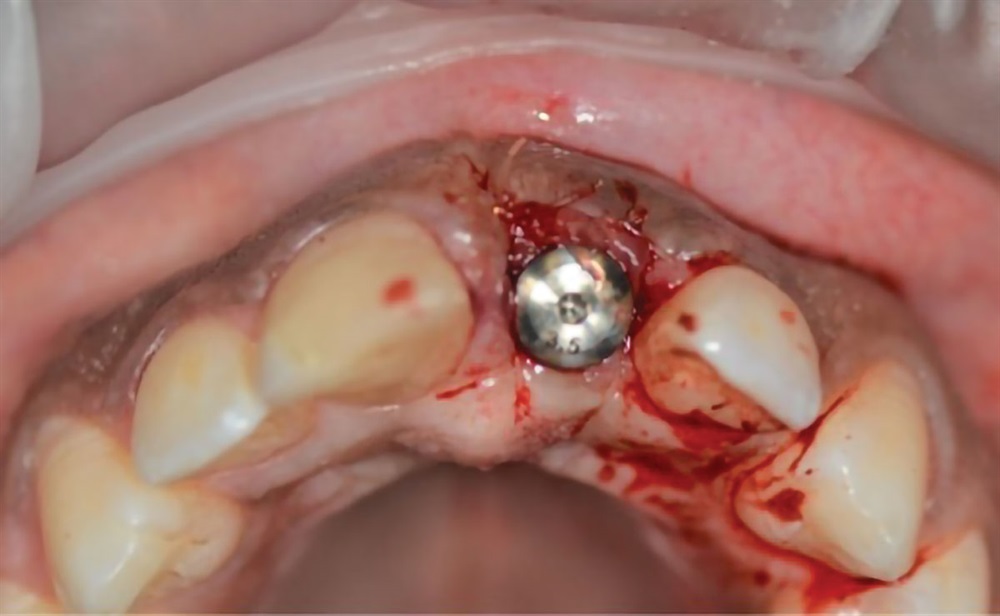

This remains one of my favorite cases because it really displays the success one can have with anterior implant cases. I was using a modified “dual zone therapy” technique (developed by Drs. D.P. Tarnow and S.J. Chu), which I have found to have great utility in an office where making immediate provisionals does not fit the workflow.

After

Horton Favorite Case